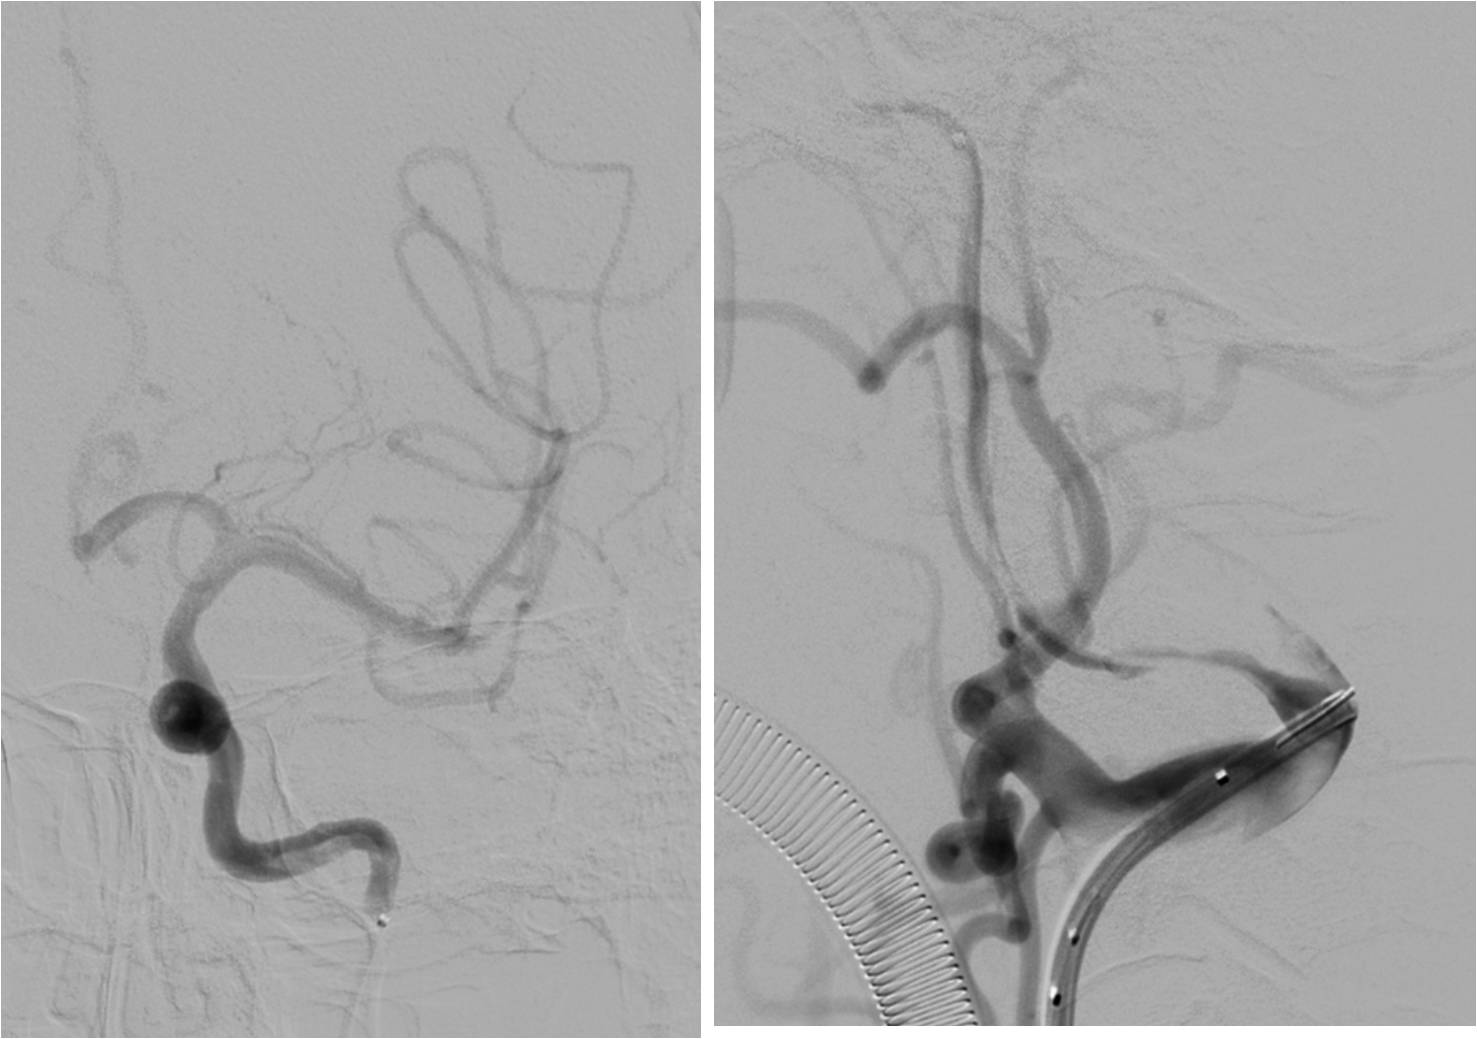

》男性,43岁,头痛、头晕伴发作性意识不清10余天入院。脑电图异常,查体无阳性体征。入院诊断“病毒性脑炎”。

》入院第3天,突发混合型失语伴右侧肢体活动不灵。

》头MRI+MRA:左侧岛叶斑片状异常信号,左侧颈内动脉不显影,左侧大脑中动脉显影较淡,远端分支较少。

》重点脑血管造影

》全麻下手术